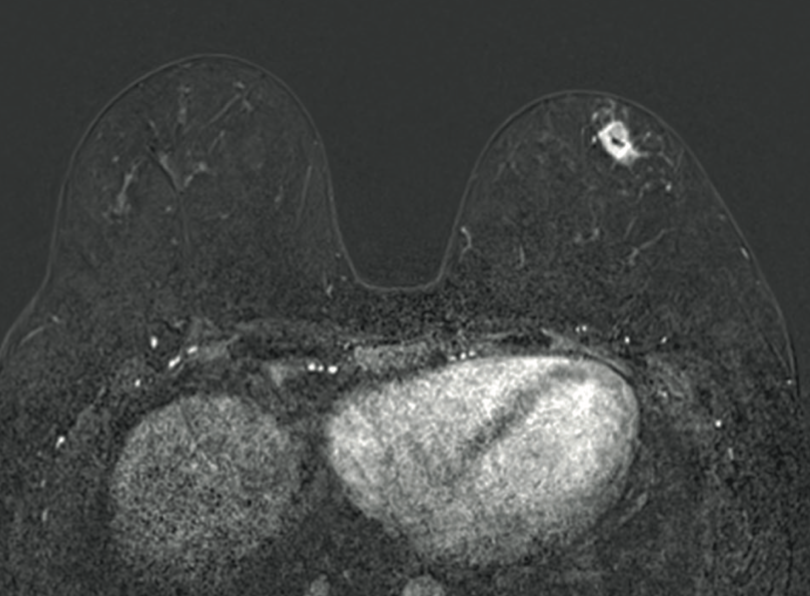

Diego Soto V, Melissa Pavez K, Sebastián Morales Z.

|